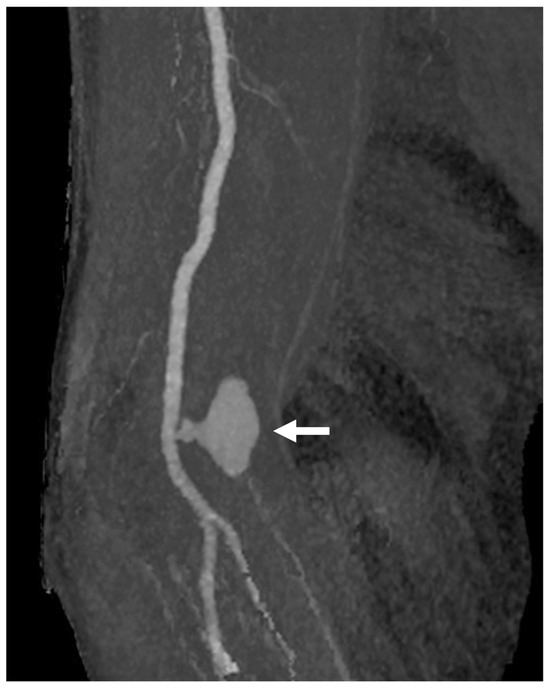

Figure 5. Pseudoaneurysm formation following TBA CAS. CTA demonstrates pseudoaneurysm formation as a complication following TBA CAS. In this case, a 6Fr guide sheath (outer diameter 2.7 mm) was inserted into the brachial artery (puncture size 2.7 mm). The pseudoaneurysm was subsequently treated with a thrombin injection (arrow: the psheudoaneurysm). Abbreviations: CAS, carotid artery stenting; CTA, computed tomography angiography; TBA, transbrachial access.